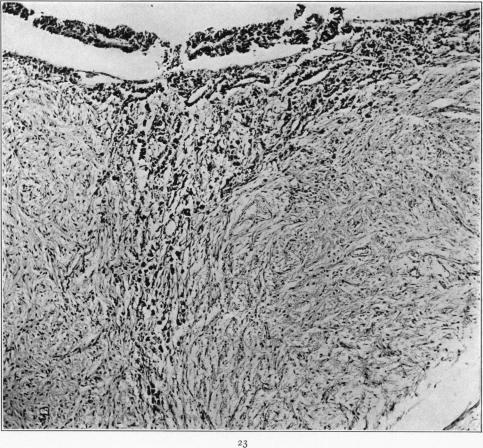

Hyperactivation of the Neurohypophysis as the Pathological Basis of Eclampsia and Other Hypertensive States.

Am J Pathol. 1934 Mar;10(2):145-176.31.

Hyperactivation of the Neurohypophysis as the Pathological Basis of Eclampsia and Other Hypertensive States.神经垂体的过度激活作为子痫及其他高血压状态的病理基础